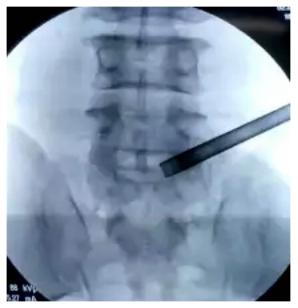

椎间孔镜手术

术者

唐都医院脊柱神经外科王鹏教授

术中